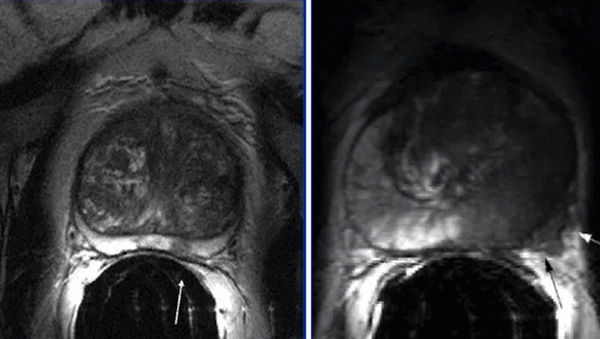

Пациент К., 1965 года рождения, при плановом обследовании в поликлинике по месту жительства в марте 2017 г. выявлено повышение уровня ПСА до 6,5 нг/мл, в связи с чем в ГКБ № 29 Москвы выполнена трансректальная биопсия предстательной железы, гистологически верифицирована ацинарная аденокарцинома 6 (3+3) баллов по Глисону. Больной самостоятельно обратился в МНИОИ им. П.А. Герцена. При пересмотре стекол препаратов биопсии предстательной железы в условиях патоморфологического отделения МНИОИ им. П.А. Герцена на фоне гиперплазии предстательной железы с очагами атрофии в 5 фрагментах из 12 выявлен рост ацинарной аденокарциномы 7 (4+3) баллов по Глисону, занимающей до 100% площади столбиков. По данным УЗИ и МРТ малого таза, предстательная железа размером 42×34×30 мм, объемом до 30 см 3 (рис. 3). Рис. 3. Магнитно-резонансная томограмма малого таза.

В периферической зоне правой доли определяется очаг раннего накопления контрастного препарата 13×10 мм без инвазии в капсулу железы и семенные пузырьки. В полости малого таза измененные лимфатические узлы не выявлены. При пальцевом ректальном исследовании предстательная железа не увеличена в размере, не деформирована, эластической консистенции, без пальпируемых узловых образований, междолевая бороздка сглажена. Слизистая оболочка прямой кишки над железой подвижна. Другой очаговой опухолевой патологии при комплексном обследовании не выявлено. На основании обследования установлен клинический диагноз: рак предстательной железы I стадии сТ2аN0M0. Больной обсужден на консилиуме с участием хирурга, химиотерапевта, лучевого терапевта и онколога: учитывая размер, локализацию и распространенность опухолевого процесса, отсутствие отдаленных и регионарных метастазов, рекомендовано хирургическое лечение. 10.04.17 больному выполнено хирургическое лечение в объеме радикальной простатэктомии, расширенной тазовой лимаденэктомии. Послеоперационный период протекал гладко, без особенностей. При контрольном УЗИ органов малого таза и вен нижних конечностей от 17.04.17 в полости малого таза объемных образований не выявлено. Поверхностные и глубокие вены обеих конечностей проходимы, без тромбоза и флебита. По данным цистографии от 17.04.17, подтверждена герметичность везикоуретрального анастомоза, в связи с чем 19.04.17 уретральный катетер удален, восстановлено самостоятельное мочеиспускание. Проведены антибактериальная, инфузионная, симптоматическая терапия и профилактика тромбоэмболических осложнений с положительным эффектом. Послеоперационная рана зажила первичным натяжением.